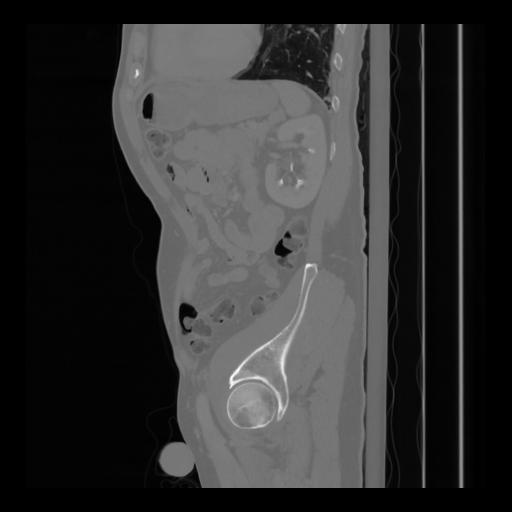

36 CUERPO,CE,Sagittal,3.000,CUERPO,Sagittal,